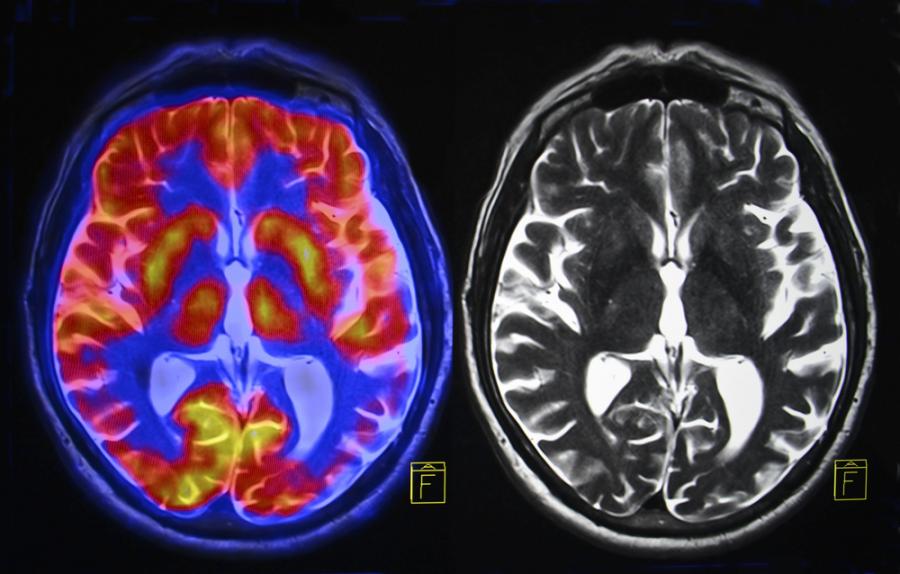

Използваме само 10 процента от мозъка си

Де да беше така! Томографските изследвания на мозъка и неврохиругията досега не са открили никакви "спящи зони". Твърдението най-вероятно датира отпреди век: психологът Уилям Джеймс заявил, че се съмнява дали средния човек използва и една десета от интелектуалния си потенциал. Всъщност съвременните изследвания показват, че непрестанно използваме много повече от 10% от нашето сиво вещество. Фактът е, че нито една област от човешкия мозък не е напълно пасивна винаги.